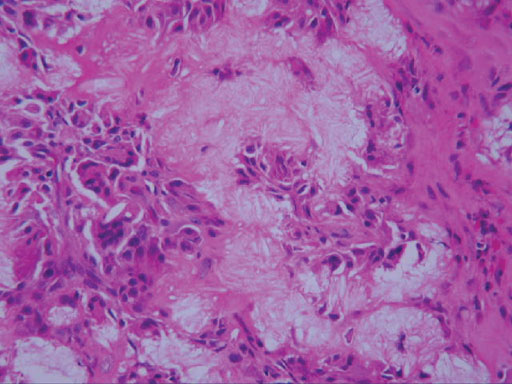

• 図7 病理組織像

滑膜性骨軟骨腫症の術前診断で手術が行われ,腫瘤摘出と中頭蓋底骨の側頭筋弁による充填が行われた.病理組織学的には線維化,異物型巨細胞,類円形の組織球系細胞に加え,多数の角材?針状結晶がみられ,ピロリン酸カルシウムの結晶沈着症の所見であった.